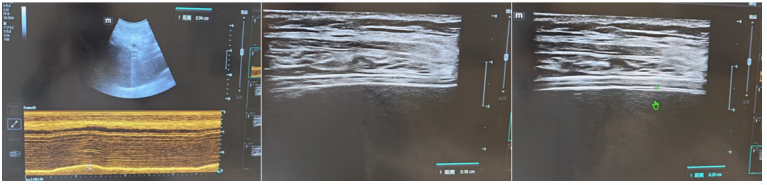

床旁超声提示患者心脏功能良好,左右心比例协调(1)综合超声(1)和相关化验结果,判断患者为脓毒性休克(分布异常性休克)

1  患者血流动力学参数

1  患者超声检查结果

膈肌超声显示:隔肌厚度0.18 cm,膈肌厚度变化率为10%,膈肌活动度为0.94 cm(图6)。膈肌功能评估提示膈肌活动度减弱;自主呼吸试验(SBT)无法通过,预估短时间拔除气管插管困难,遂予气管切开。

图片

6  患者膈肌超声